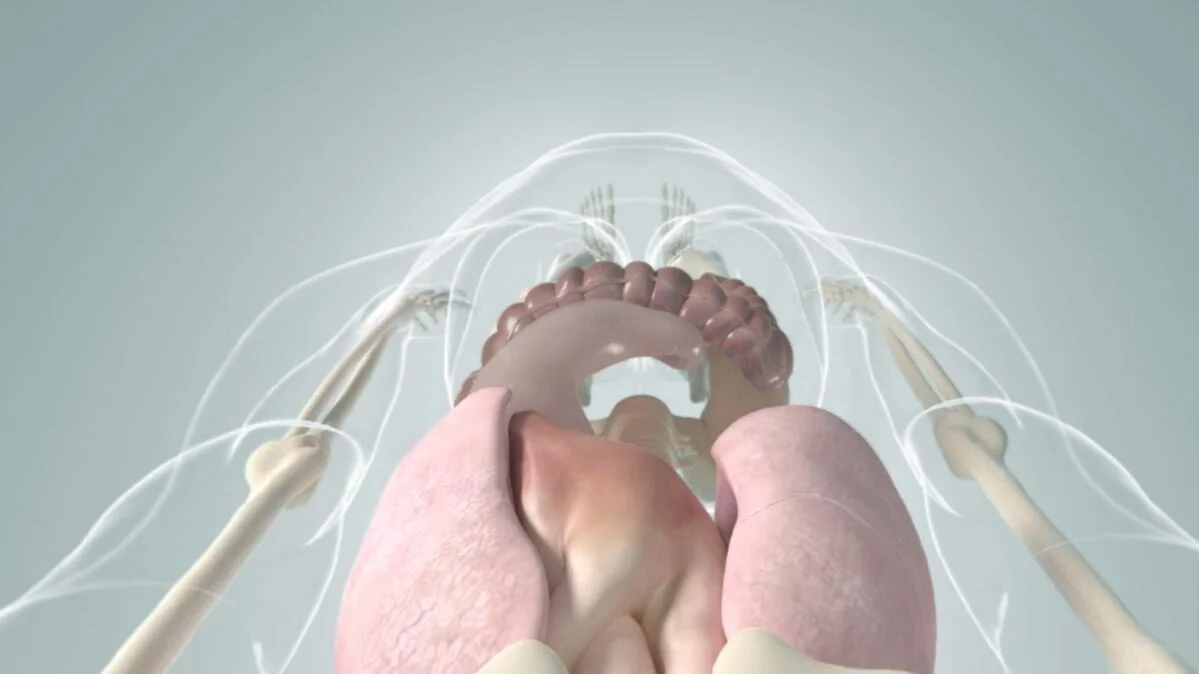

Weekly Research Animations

Running series of animated visual abstracts, Quick Takes, created for The New England Journal of Medicine as part of a team of illustrators, medical writers, and scientists. These short, iconographic animations aim to succinctly describe clinical trials and increase the awareness and understanding of important research findings.

Adopting The Journal’s visual style and asset library, I am responsible for the entire production process including narration editing, storyboarding, layout, illustration, and animation.